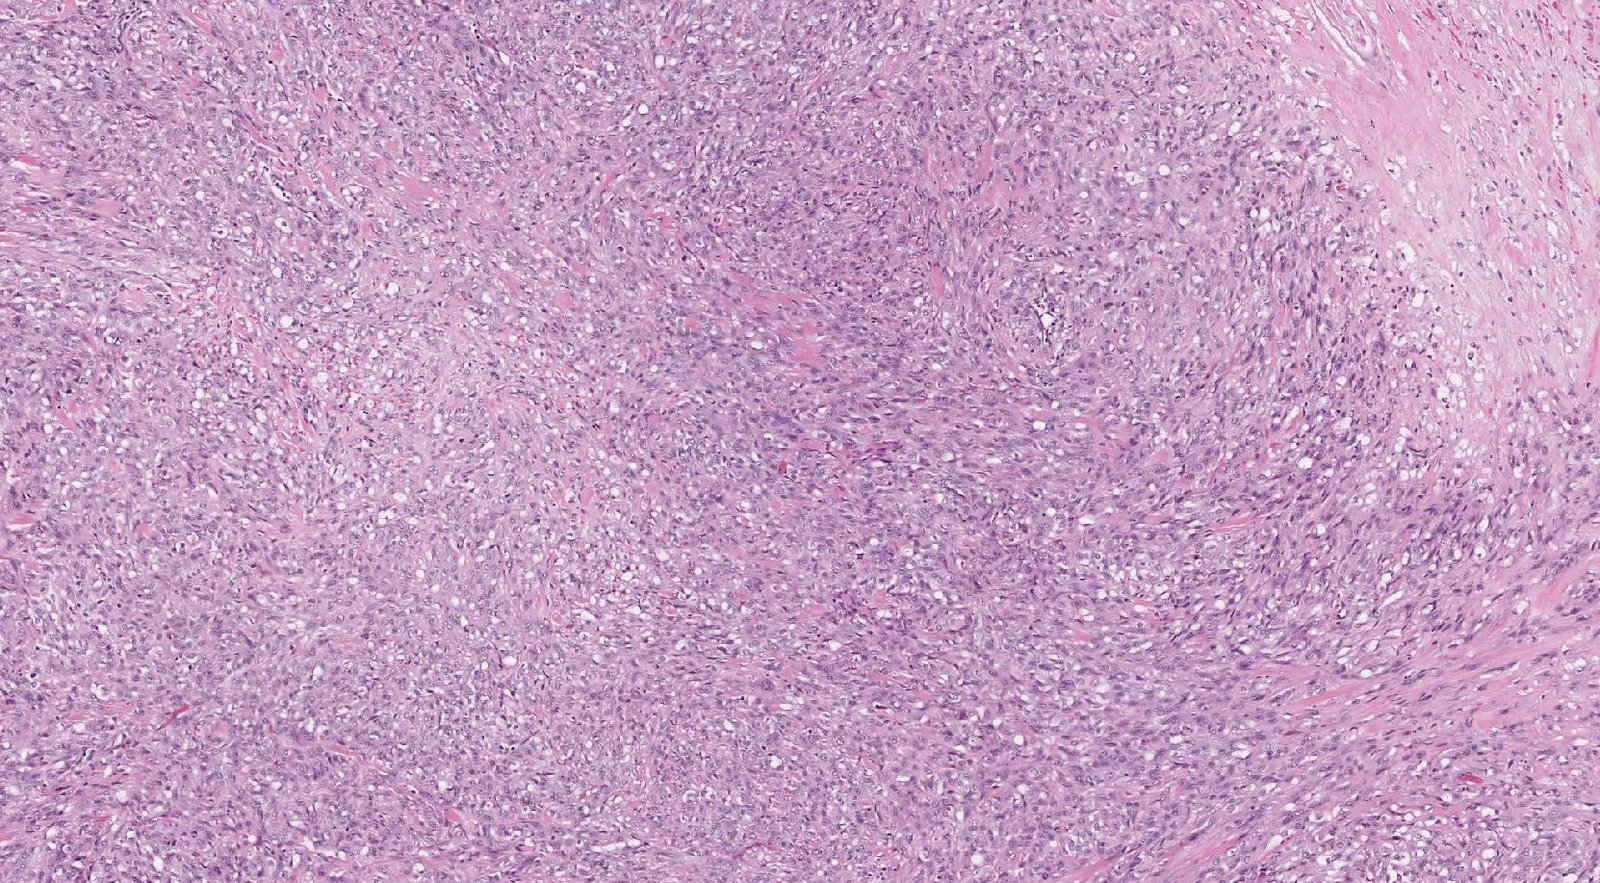

Case: ArmLesion

Specials to Order:

Final Diagnosis: